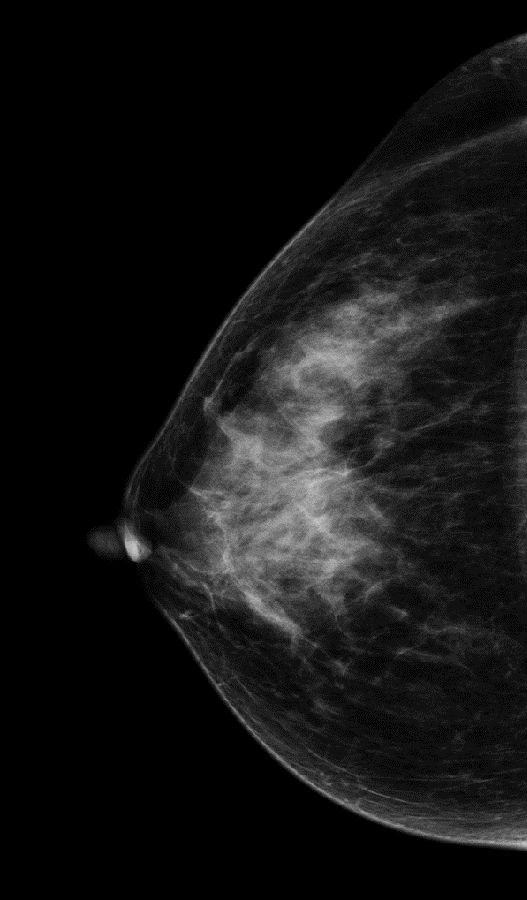

病史:患者43岁,发现右乳包块2周。

2D图像:

常规2D图像MLO位上象限见一团块状影,在CC位上并没有发现可疑异常密度影,在V-Preview图像和tomo图像上我们可以清楚发现病变边界不清见长短不一毛刺,呈星芒样改变。

右乳上方略偏外局限致密影BI-RADS 4B 。

在TOMO图像上对星芒样病灶周边情况显示明显优于2D图像,最后病理证实右乳浸润性导管癌。